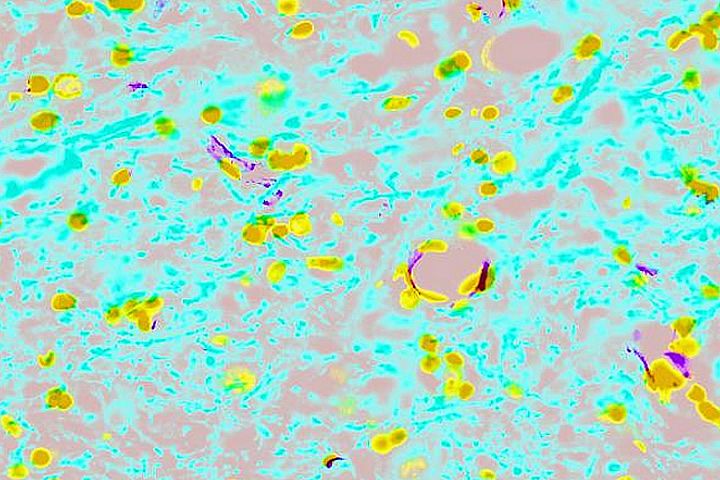

Las doctoras Serrano y López Dolado explican que su trabajo consistirá en poner en contacto los distintos nanomateriales y dispositivos integrados de mayor complejidad con células del sistema nervioso central. Este procesos se realizará inicialmente in vitro, en placas de cultivo. Si las respuestas son positivas, indican estas profesionales, la idea es que en fases más avanzadas se implante en un modelo experimental de lesión medular en ratas.

Para acercarse a una posible solución, las profesionales destacan que se van a introducir nanomateriales, con propiedades sensoras y de estimulación eléctrica, que van a permitir investigar “en las dimensiones propias de los componentes celulares, pues son materiales de muy pequeño tamaño al igual que las estructuras que se están dañando”. En la actualidad, dicen las doctoras, esto no es posible "con la tecnología existente".